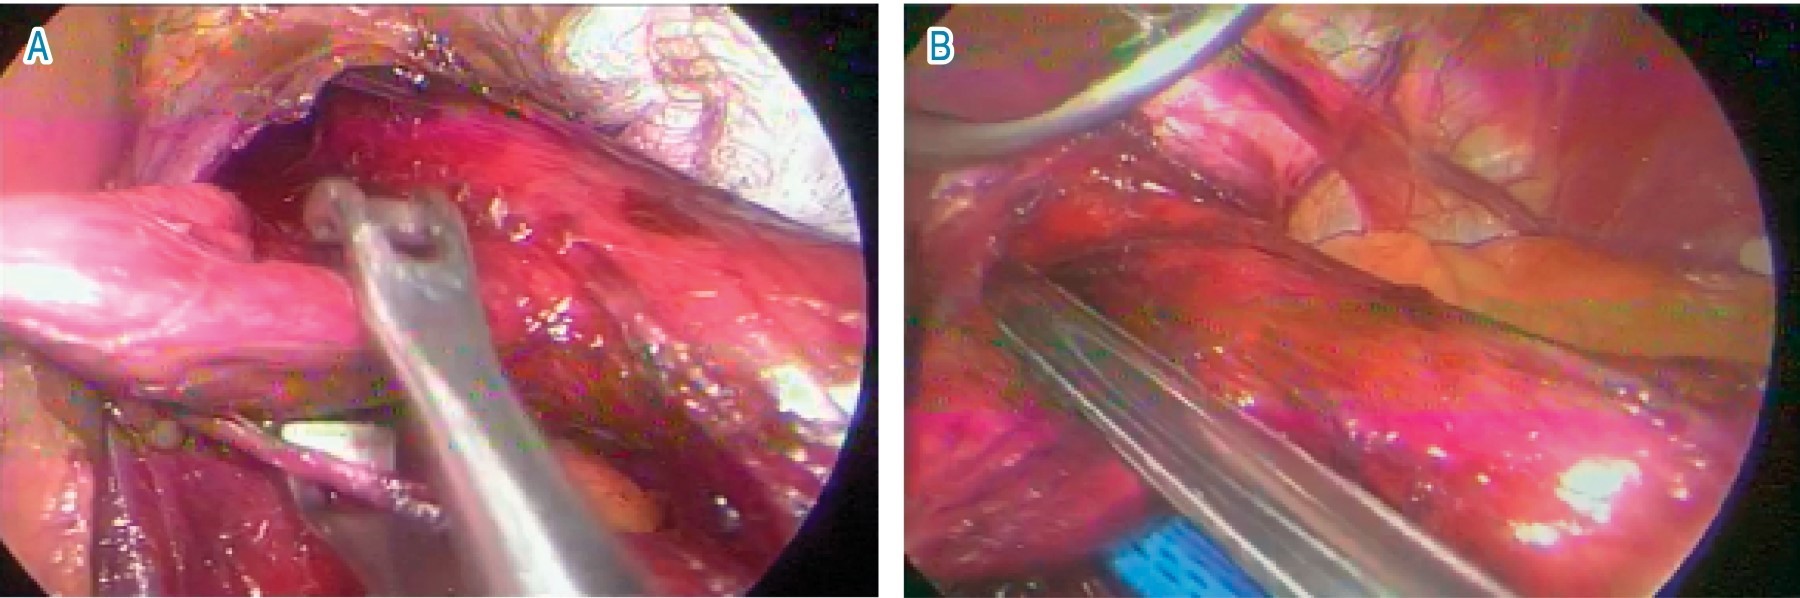

Una vez completado el protocolo, se decide llevar a cirugía, realizando un abordaje laparoscópico y transabdominal, colocando dos puertos de 10 mm, dos puertos de 5 mm y el separador hepático, como se usa de manera tradicional para funduplicatura, se inició disecando la pars flácida y, posteriormente, se disecaron vasos cortos, se creó una ventana retroesofágica y se colocó un Penrose 1/4 de pulgada para tracción, para así poder realizar una adecuada disección de los pilares diafragmáticos y del esófago; una vez disecado encontramos un divertículo posterolateral derecho a 3 cm de la unión gastroesofágica, el cual medía 3 × 3 cm, se disecan las adherencias al mismo y se separa el nervio vago, posteriormente se realiza corte con engrapadora lineal, EGIA cartucho morado y se procede a realizar cierre de los pilares diafragmáticos con punto en equis, con sutura prolene 2/0, se realizó funduplicatura laparoscópica tipo Nissen, colocando sonda de calibración número 40 French, con un tamaño de 5 cm y fijado con 3 puntos simples de prolene 2/0 y se da por terminado el procedimiento (Figura 4).

Figura 4